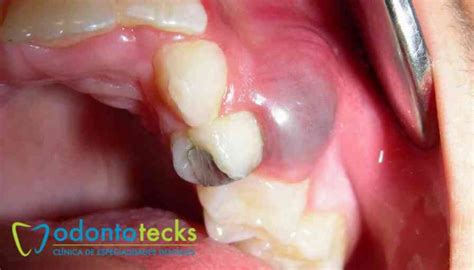

Muchos pacientes acuden a la clínica preocupados por la aparición de un bulto en la encía, el cual puede presentar diferentes formas y síntomas, ya que existen distintos tipos producidos por causas de variados orígenes. Por lo general, suele ser un quiste en la boca.

Los quistes en la boca suelen ser asintomáticos y se detectan por la presencia del propio bulto. Antes de la aparición del quiste, la acumulación de pus (absceso) puede ocasionar dolor. Por ello, cuando se forma el quiste dental, al ser una infección con un proceso crónico y no agudo, el dolor desaparece, quedando, a veces, inflamación y pequeñas molestias.

- Puede aparecer una protuberancia semiblanda en la encía cuyo interior está formado por pus.

El primer paso para un diagnóstico adecuado de un quiste bucal es la revisión y exploración clínica que realizan nuestros dentistas. Durante esta revisión periódica, se examina minuciosamente la boca, las encías y los dientes en busca de cualquier anormalidad, como bultos, hinchazones o cambios en el color de los tejidos.